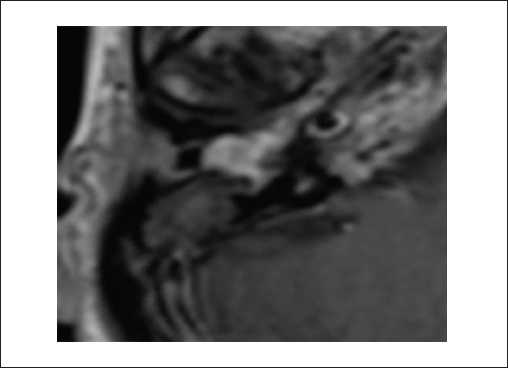

Пациенты второй группы предъявляли жалобы на снижение или отсутствие слуха с пораженной процессом стороны, периодическое онемение лица. При отоскопии у пациентов определялось бордовое пульсирующее объемное образование, выпячивающее кнаружи барабанную перепонку. По данным лучевых исследований, на КТ височных костей определялся мягкотканный субстрат, заполняющий барабанную полость и распространяющийся в антрум и клетки сосцевидного отростка. Крыша барабанной полости была истончена. Костная стенка канала внутренней сонной артерии у пациентов с типом В3 не прослеживалась. На уровне гипотимпанума определялось мягкотканное образование, которое разрушало костные стенки (рисунок 3). На МРТ головного мозга и мягких тканей шеи с контрастированием определялось распространение образования в клетки сосцевидного отростка, без инвазии в луковицу яремной вены и внутреннюю сонную артерию. В клетках сосцевидного отростка определялись следы жидкости (рисунок 4).

Рисунок 4. МРТ головного мозга и мягких тканей шеи, Т2-ВИс подавлением сигнала от жировой ткани, в корональной плоскости. Параганглиома, тип В.